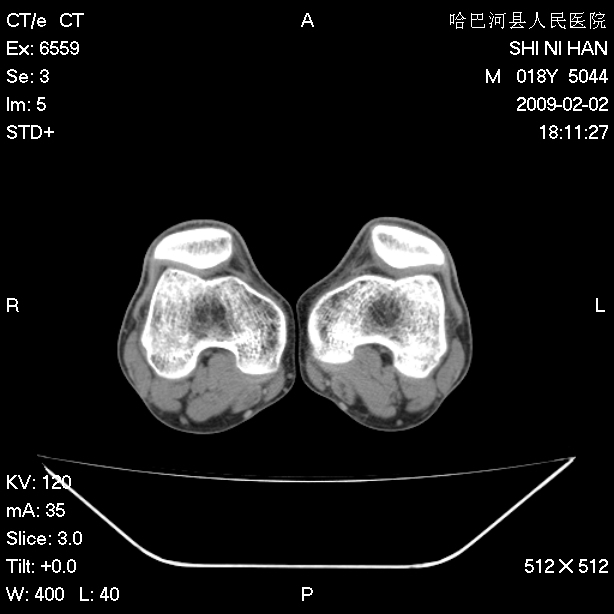

标题: CT17889:外伤后右膝关节反复疼痛3年余 [打印本页]

标题: CT17889:外伤后右膝关节反复疼痛3年余

ct未见明显异常。关节腔未见明显积液,半月板未见明显撕裂。但最好还是mri看看韧带及半月板情况。